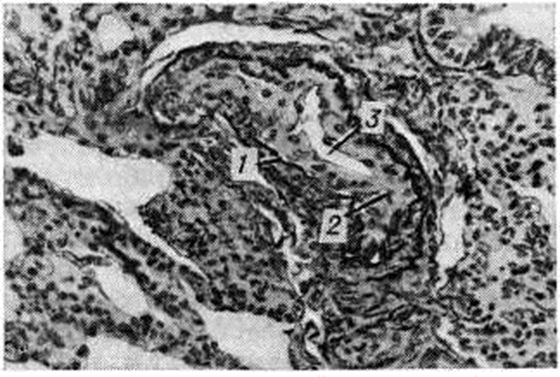

Прекапиллярная форма наиболее часто развивается на фоне хронический болезней лёгких, сопровождающихся эмфиземой со склерозом альвеолярных перегородок. Возникающее при этом сопротивление кровотоку в капиллярах приводит к переполнению кровью мелких артерий, вследствие чего просвет их растягивается, циркулярный мышечный слой истончается и вместе с тем за пределами внутренней эластической мембраны формируется более или менее массивный продольный мышечный слой (рисунок 1 и 2). В венозном русле отмечается атрофия мышечных элементов, просвет вен спадается, внутренняя оболочка склерозируется.

При гиперволемии малого круга (дефект межжелудочковой перегородки, открытый аортальный проток и другие), помимо значительной гипертрофии средней оболочки мелких ветвей лёгочных артерий с их миоэластозом и последующим миоэластофиброзом, при высокой степени Гипертензия малого круга кровообращения со стороны внутренней оболочки в артериях отмечается большое количество крупных пикринофильных гломусных клеток с крупным ядром (рисунок 3), способных выделять ацетил холин, холинэстеразу, адреналин, которые воздействуют на периферическое кровообращение. В зарубежных исследованиях эти образования часто неправильно трактуют как артерииты или фиброз интимы.